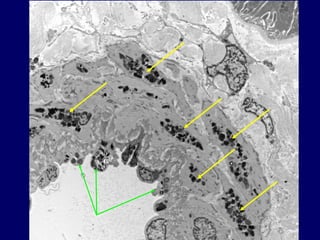

Distal Tubules

20

21

Tubule

Distal Tubule

PTC - Endo

TBM

22